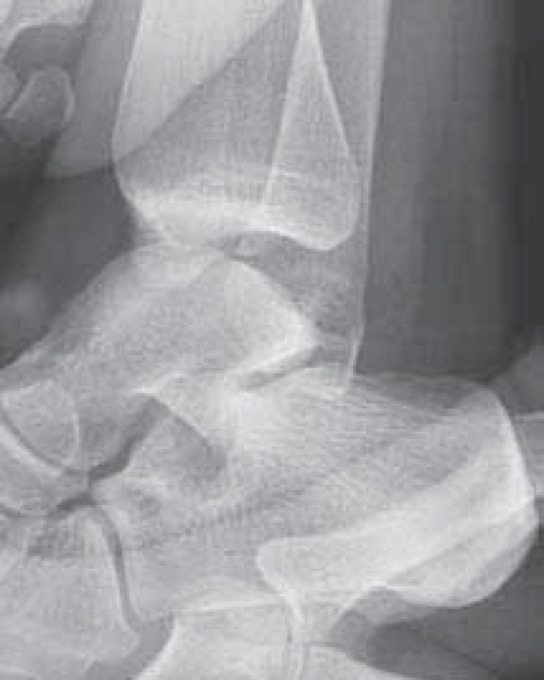

Xrays

Osteochondral lesions

Loose bodies

Stress Xrays

![]() |

ATFL tear

CFL tear